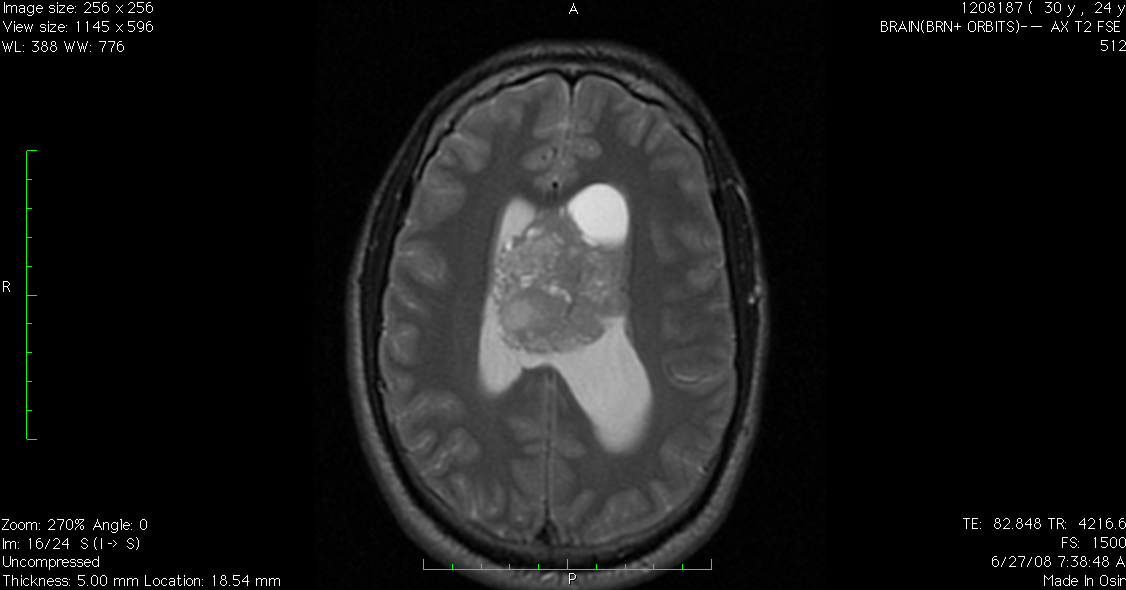

Neither of us actually said the words, but I know we were both thinking it – there was, and always will be, a possibility of a recurrence. It was suggested by the eye doctor that at my next MRI, I have imaging done of my orbits, to see the inner workings of my eyes. Another mystery to solve, and when I shared this news with my family, we all said “only me.”

With many thanks to the wonderful team at the team at Yale, they scheduled me an appointment and got me in for scans last week. Double vision, double scans. Normally, I have a brain scan but this time, we added a scan of the orbits to see the inner workings of my eyes.

That following Tuesday, we arrived at Yale for a 7am MRI and while I lay on the cold slab of metal with the awful noises and banging from the machine, the only thing I could focus on was trying to breathe through the COVID face mask and the metal frame an inch above my face. Within a few hours, I received the long-awaited call and heard the news I knew was coming – you have a beautiful brain and the shunt is doing what it’s supposed to do. These words were such a relief to hear, but it led to the next question – why am I still seeing double then? Time will tell, as I am seeing a neuro-ophthalmologist this coming week.